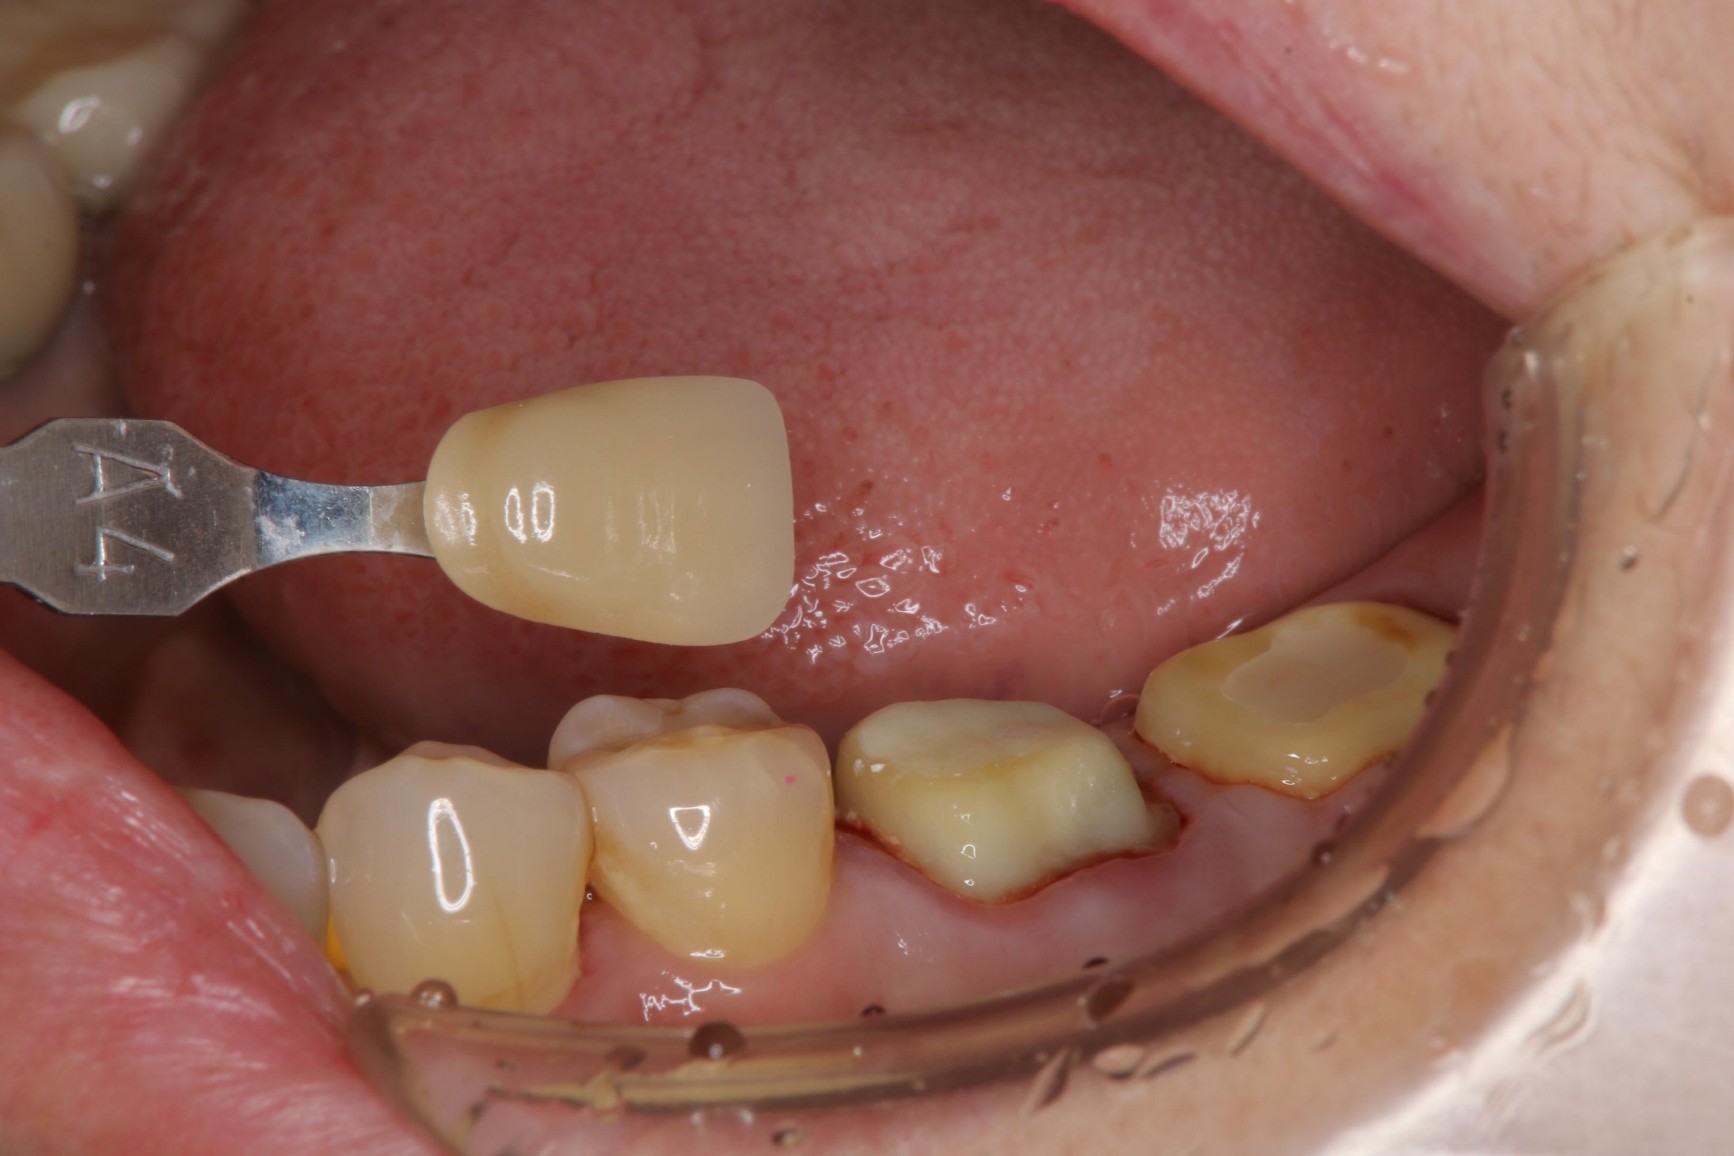

膺復前評估牙齦、牙齒狀態

照相比色